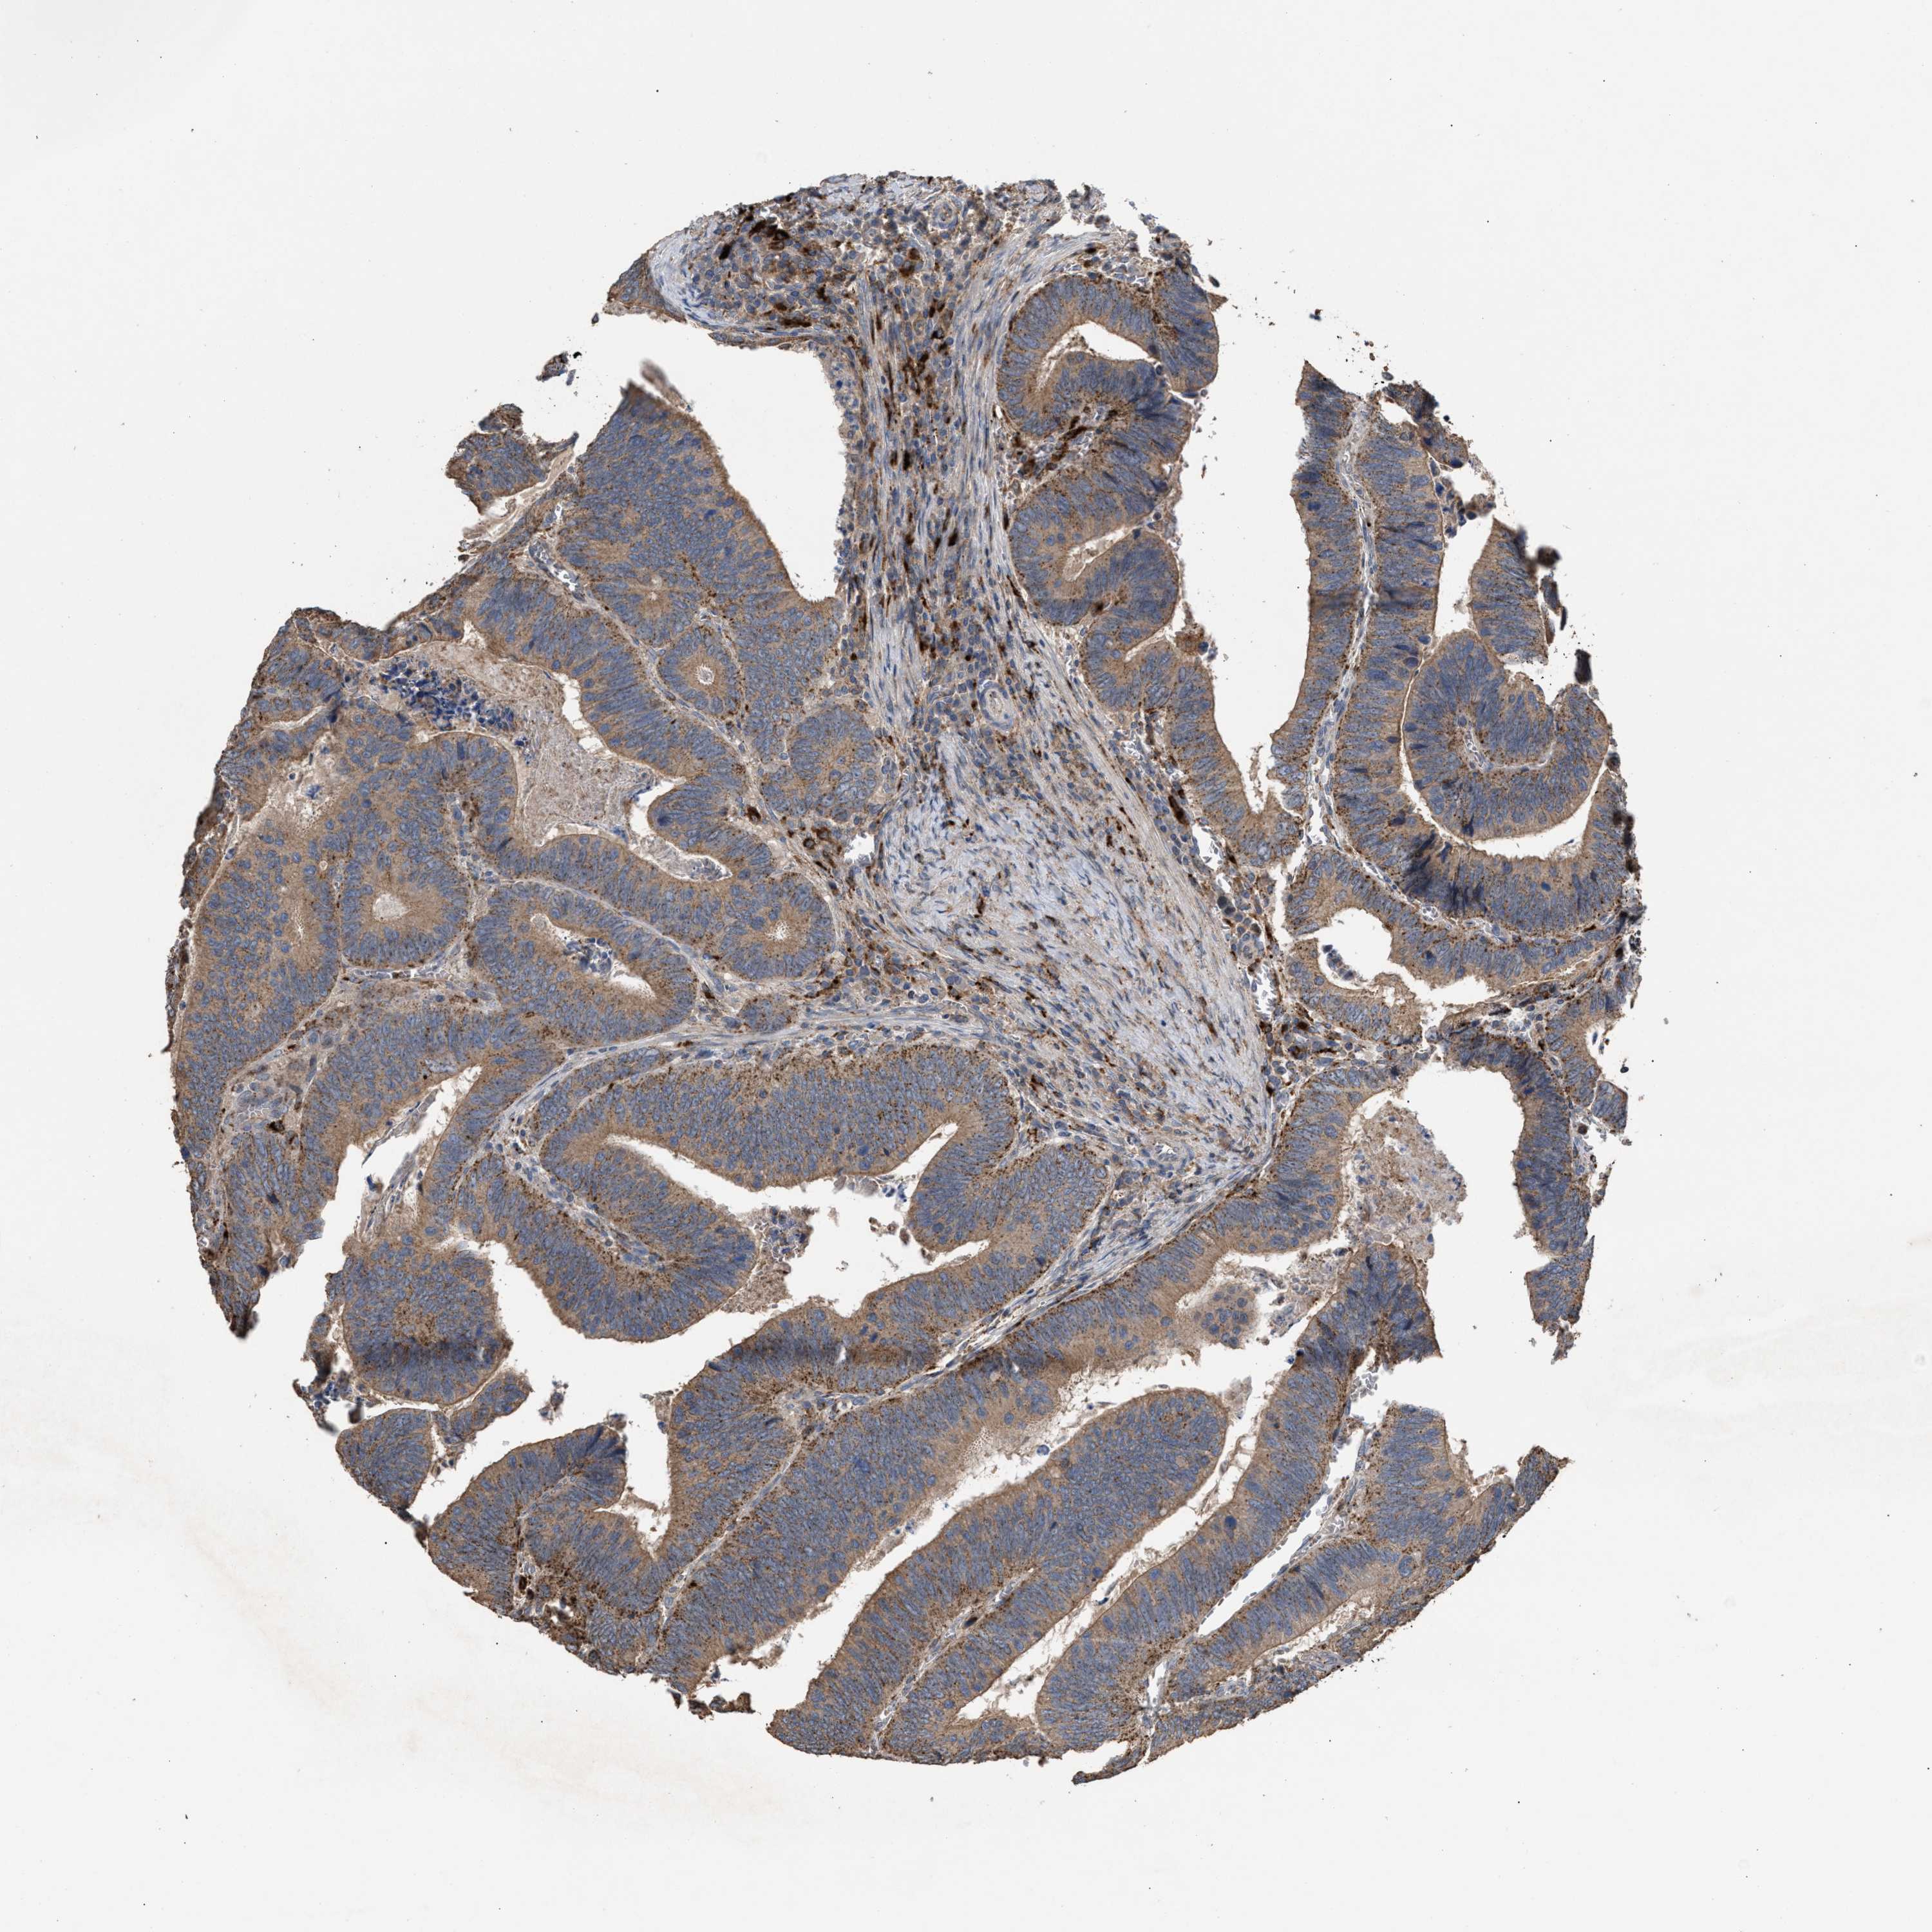

CANCER COLORECTAL CANCER Show tissue menu

Colorectal cancer

Human cancer

Colon adenocarcinoma

Rectum adenocarcinoma